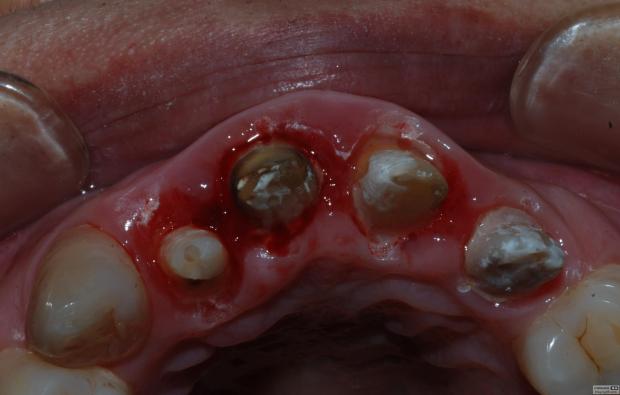

病例1 由于根管充填不完善造成修復(fù)體拆除

修復(fù)后出現(xiàn)根尖周炎癥狀 根管再治療后病變愈合